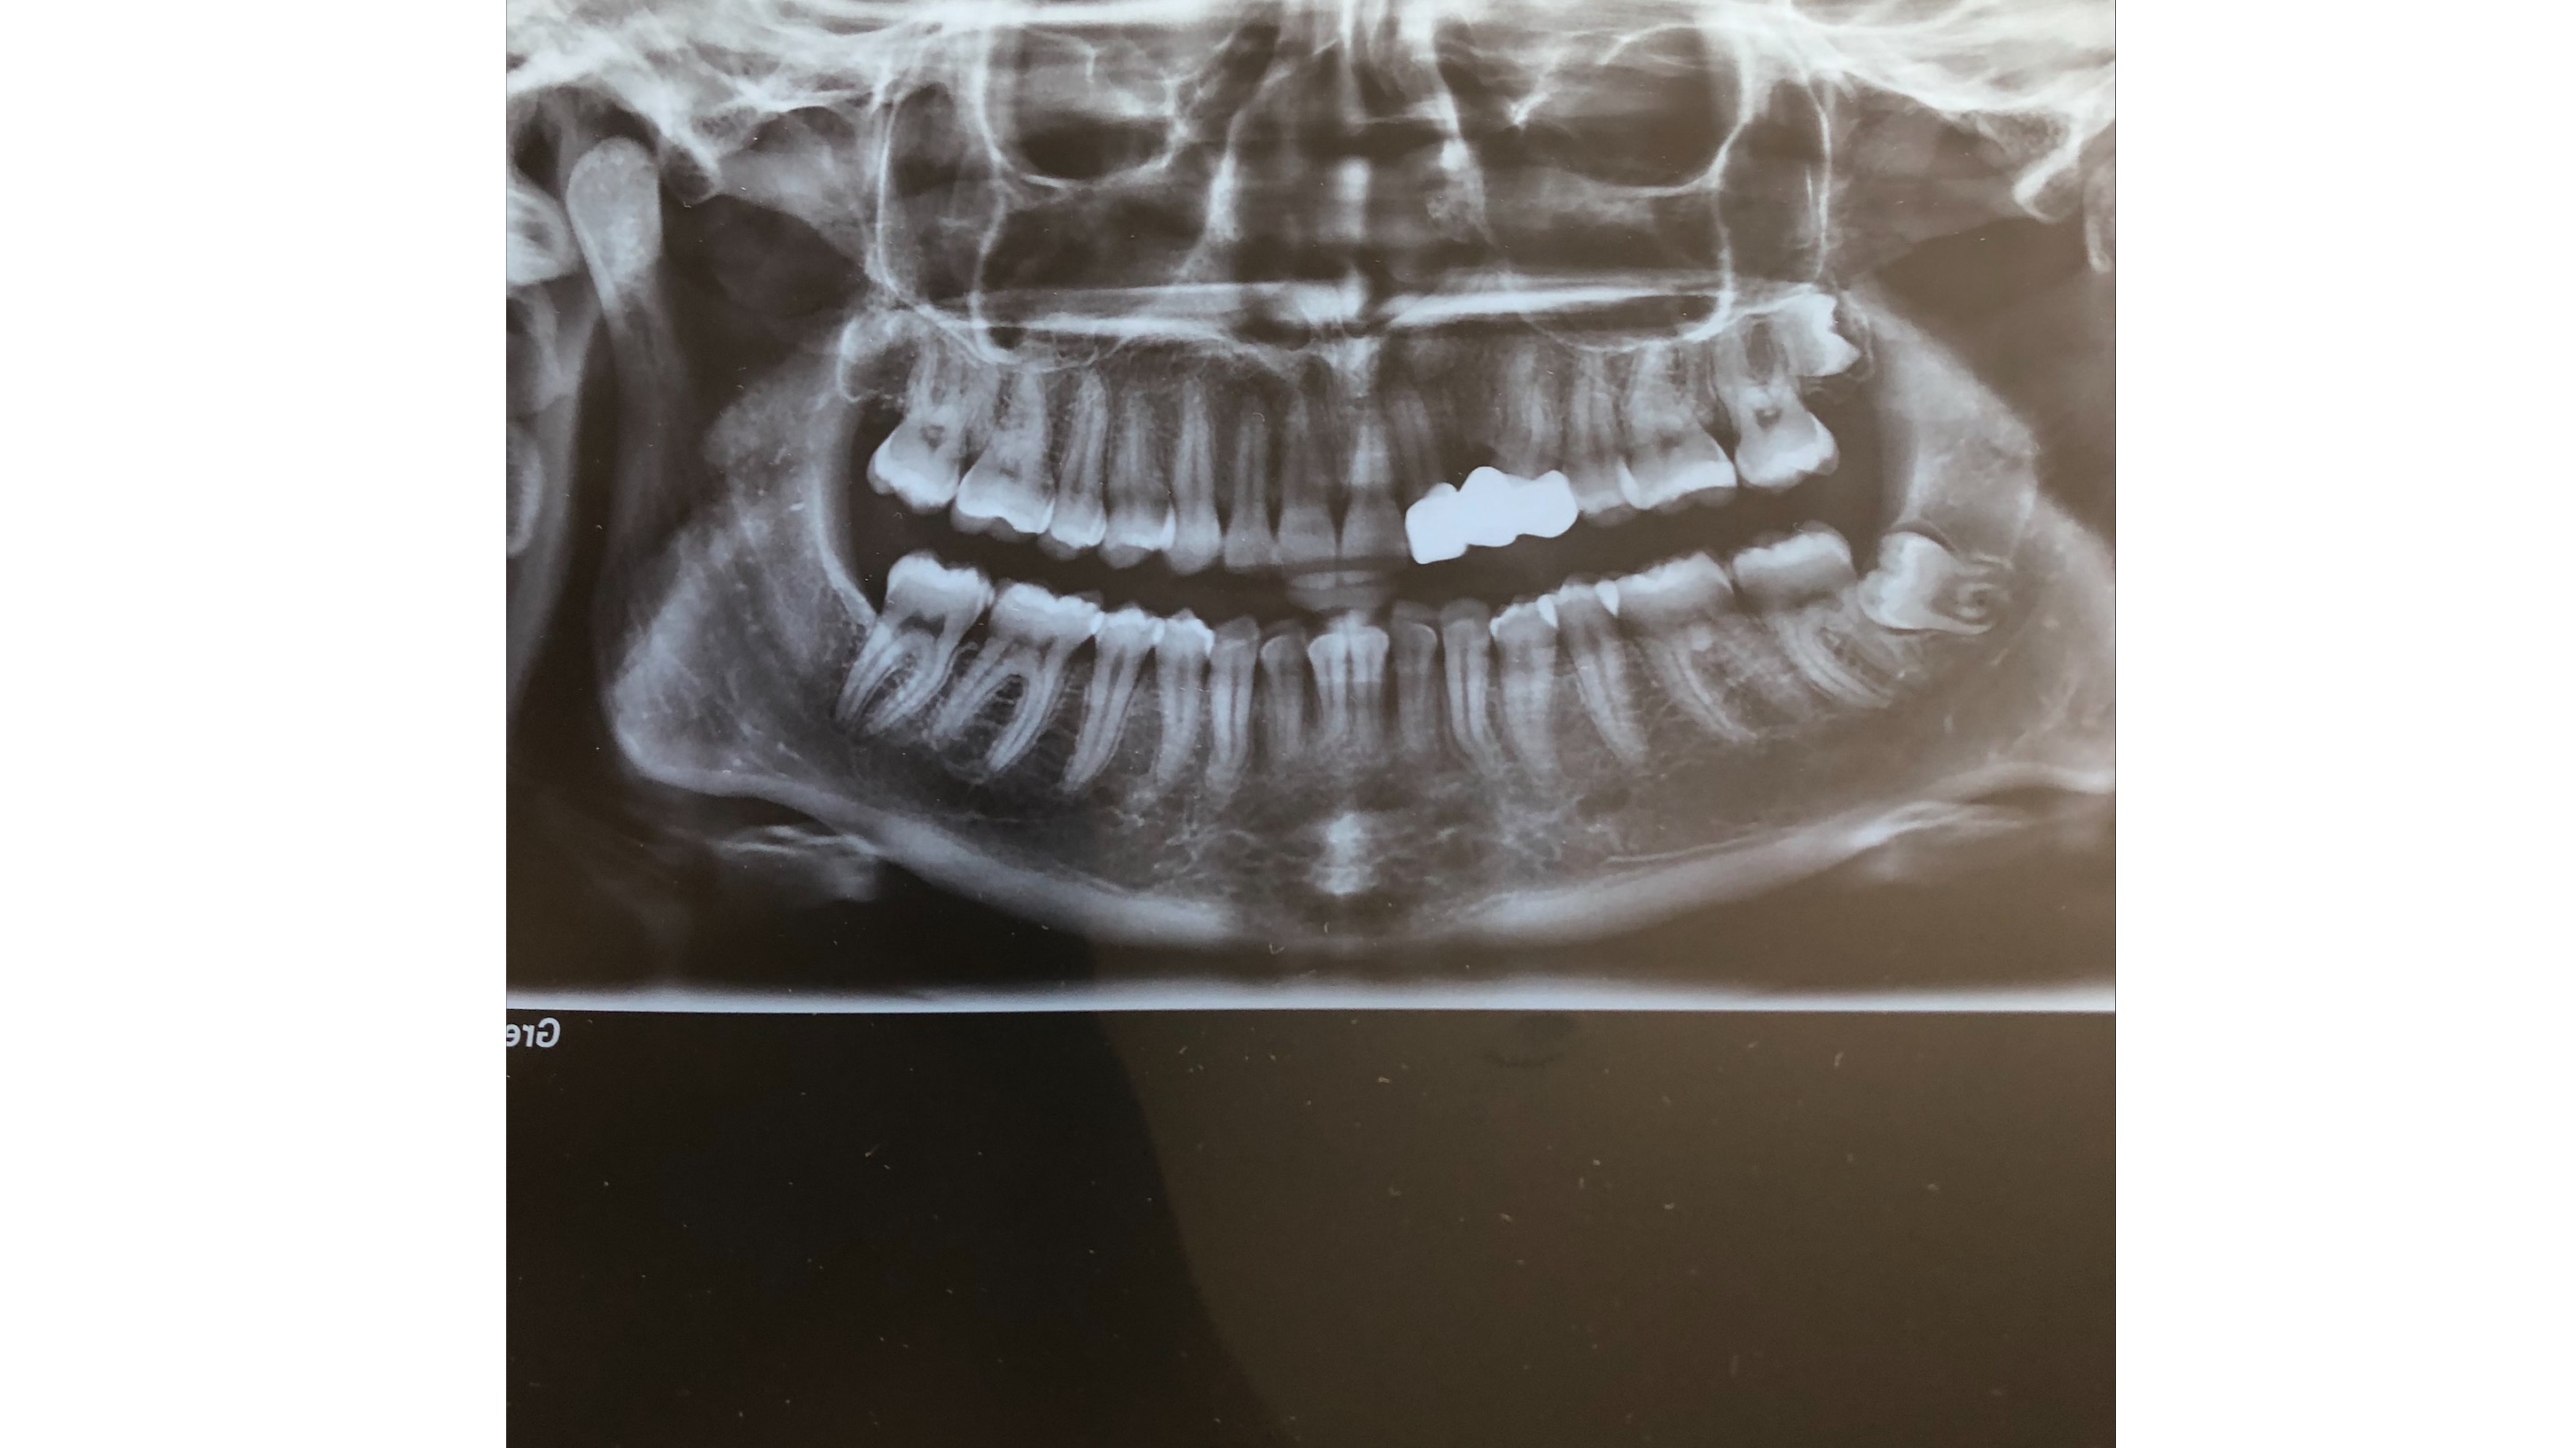

I had a dental procedure take place in 2019, which has cost me 4 years of my life living in chronic pain, misplaced jaw, breathing issues, fatigue and basically bed ridden terms. After many treatments that haven’t helped, many referrals to medical professionals, I am now booked in to have Double Jaw Surgery in July 2024 to fix my misaligned jaw, my uneven non existent bite, my headaches, neck issues as well as most importantly my breathing / airways.

Wisdom teeth removal: $800

I had a dental procedure take place in 2019, which has cost me 4 years of my life living in chronic pain, misplaced jaw, breathing issues, fatigue and basically bed ridden terms. After many treatments that haven’t helped, many referrals to medical professionals, I am now booked in to have Double Jaw Surgery in July 2024 to fix my misaligned jaw, my uneven non existent bite, my headaches, neck issues as well as most importantly my breathing / airways.

Wisdom teeth removal: $800